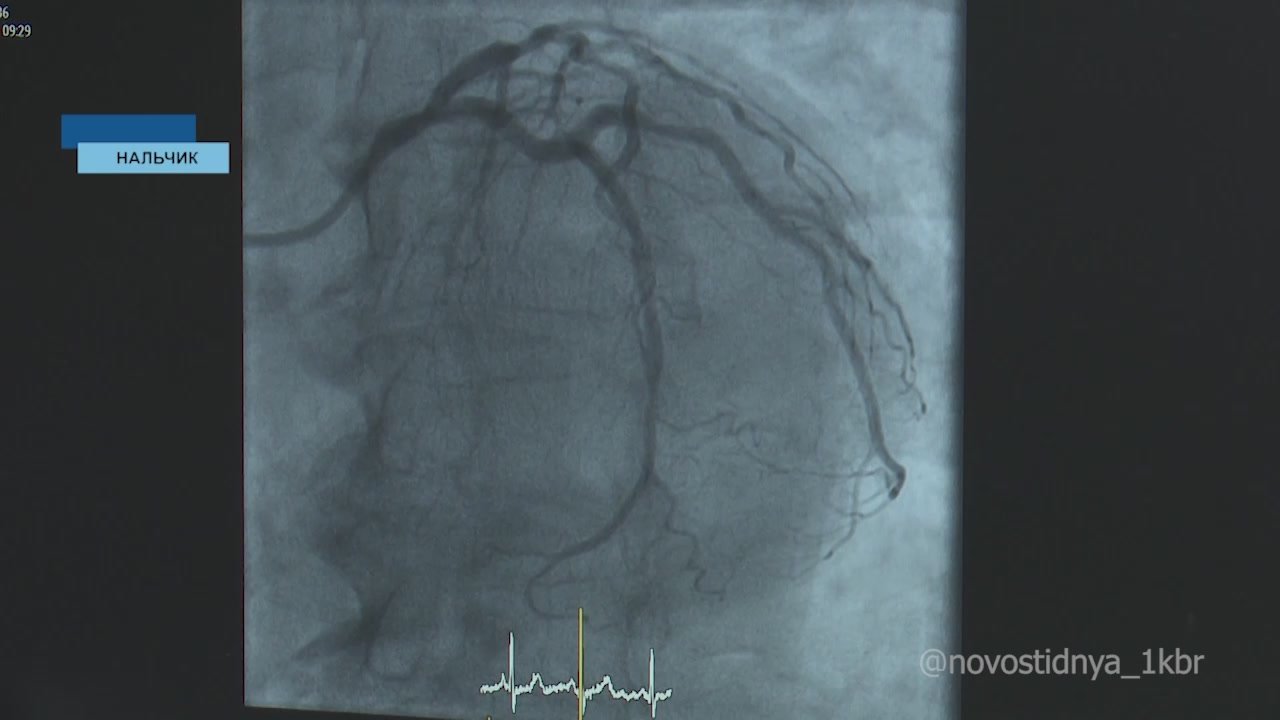

Праздники праздниками, но надо еще задуматься о своем здоровье. Республиканский Минздрав предупреждает о риске «синдрома праздничного сердца». Особенно это касается людей с хроническими заболеваниями.

Республиканский Минздрав предупреждает о риске «синдрома праздничного сердца». Особенно это касается людей с хроническими заболеваниями.Подписывайтесь на MAX